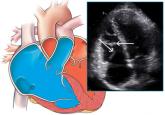

ArticleA middle-aged man with progressive fatigueAuthor:Anna M. McDivit, MDPublish date: October 1, 2009He has been taking good care of himself, but 1 year ago his ejection fraction was 60% and now it is 35%. He also has a new left bundle branch block...Read More